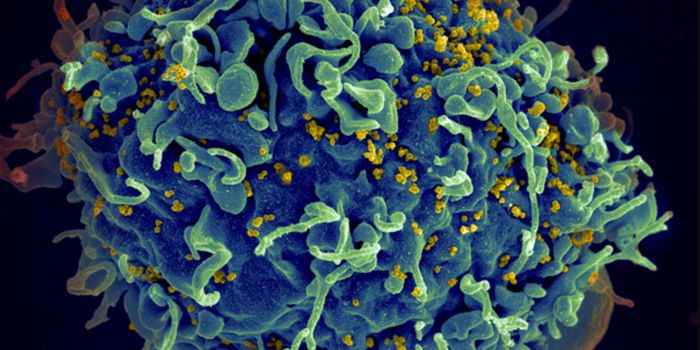

MAY 14, 2024Cell & Molecular BiologyIt's estimated that about 3.7 billion people under the age of 50 are infected with (HSV-1), which can cause oral herpes.